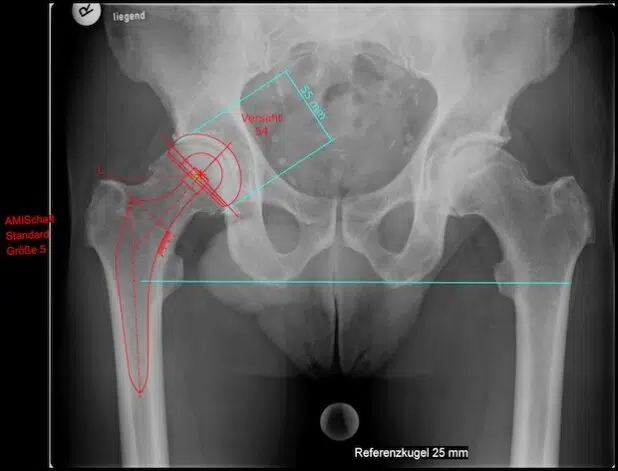

Dr. Konermann: „AMIS steht für „Anterior Minimally Invasive Surgery“ und beschreibt den optimal muskelschonenden Zugangsweg zum Hüftgelenk von vorne bei der Operation des künstlichen Hüftgelenkes. Statt einer üblicherweise ca. 20 cm langen Naht benötigen wir bei der neuen OP-Technik nur 5-8 cm. Da bei der AMIS-Hüftoperation zwischen zwei Muskelgruppen und zwischen zwei Nervengebieten zum Hüftgelenk eingegangen wird, müssen keine Muskeln eingeschnitten oder durchtrennt werden, wie es bei allen anderen Operationsmethoden der Fall wäre. So verläuft die Heilung schneller und der Patient hat weniger Schmerzen.“

Dr. Konermann: „Der wesentliche Vorteil beim direkten vorderen Zugang ist die Reduktion des Muskeltraumas. Es werden weder Muskeln quer durchtrennt noch Muskelansätze am Knochen abgetrennt. Der Erhalt der Hüftmuskeln soll eine sofortige Hüftstabilität gewährleisten. Die AMIS-Methode zum Ersatz des abgenutzten, schmerzhaften Hüftgelenks ist aus meiner Erfahrung den übrigen herkömmlichen Operationsmethoden deutlich überlegen und bringt eine Vielzahl von Vorteilen und Verbesserungen für die betroffenen Patienten, der ein neues, künstliches Hüftgelenk braucht. So dürfen die Patienten schon am ersten Tag nach der Hüftoperation aufstehen und müssen nicht länger ausschließlich auf dem Rücken liegen. Der Patient darf nach der Operation auf der Seite liegen. Körperpflege und Essen ist bereits am ersten Tag nach der OP außerhalb des Bettes im Badezimmer bzw. Sitzen am Tisch erlaubt. Die Patienten sind viel schneller wieder mobil und können das Krankenhaus nach wenigen Tagen verlassen. Auch Sportarten wie z.B. Wandern, Golfen, Radfahren, Tennis usw. sind nach sechs bis acht Wochen schon möglich.“